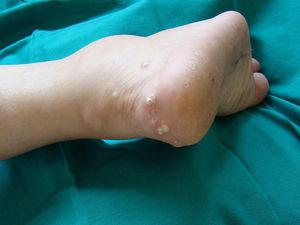

Como consecuencia del control y del tratamiento irregular, la paciente desarrolló una grave gota tofácea (con presencia incluso de tofos intradérmicos) con importantes secuelas en las articulaciones tibioastragalina, tarsometatarsiana y en las articulaciones intertarsianas, lo que configuró una grave artrosis de tobillos y de pie erizado3, así como una gran afectación de rodillas que requirió de la implantación de prótesis en ambas rodillas.

En este sentido, cabe destacar que durante toda la evolución las cifras de uricemia se han mantenido por encima del rango superior de la normalidad y se ha observado acumulación de ácido úrico (tofos) en localizaciones poco frecuentes (figs. 1–3).

Figura 3. Presencia de tofos intradérmicos en región calcánea.